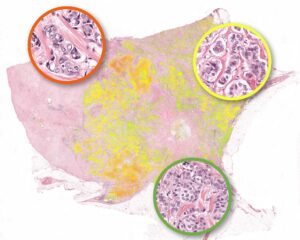

AI can already detect breast cancer better than a specialist